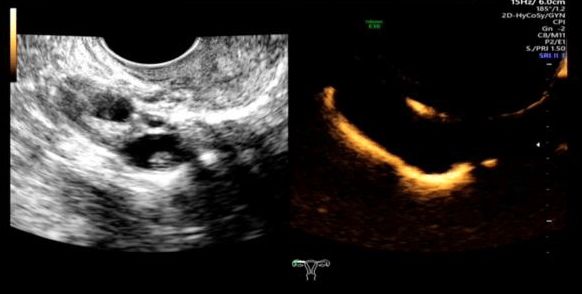

简单来说,这是一项评估输卵管通畅性的医学影像检查技术。检查时,医生会在宫腔内放置一根双腔造影管,通过推注造影剂,动态观察造影剂在宫腔、输卵管和盆腔的流动、积聚和弥散情况,从而判断输卵管的通畅度、走形以及病灶部位。通过这个快速安全的检查,输卵管的许多问题便能一目了然。

正常宫腔

宫腔底部凹陷

右侧输卵管积水